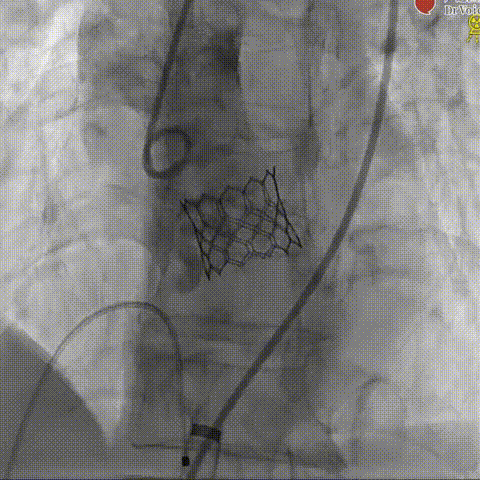

瓣膜释放

术后造影

球囊预扩

瓣膜释放后造影

球囊后扩